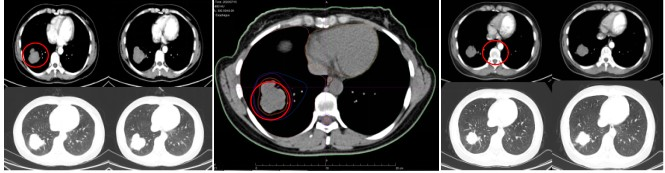

• Lung Lesion: Pre-treatment size: 4.7 cm × 5.2 cm; Post-treatment size: 4.2 cm × 3.5 cm. Evaluation: SD (Figure 5).

Figure 5: Pre-treatment size of the lung lesion: 4.7 cm × 5.2 cm; Post-treatment size on chest CT after 1 month: 4.2 cm × 3.5 cm

Evaluation of Pulmonary Lesions: Before radiotherapy, the size of the pulmonary lesion was 4.7 cm × 5.2 cm. One month after treatment, chest CT showed a reduction in size to 4.2 cm × 3.5 cm, also evaluated as SD.